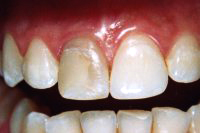

Ein rechter oberer, devitaler Schneidezahn bei einem 19-jährigen Mädchen ist stark verfärbt (Abb. 1). Der Zahn wird zuerst intern gebleicht, die alte Füllung unter Schonung der gesunden Eigensubstanz entfernt (Abb. 2) und dann mit einem weissen Zirkonoxydstift im Wurzelkanal und einer Kompositfüllung aufgebaut (Abb. 3). Der Zirkonoxydstift stabilisiert den Zahn gegen Bruch und erfüllt ästhetisch höchste Ansprüche.